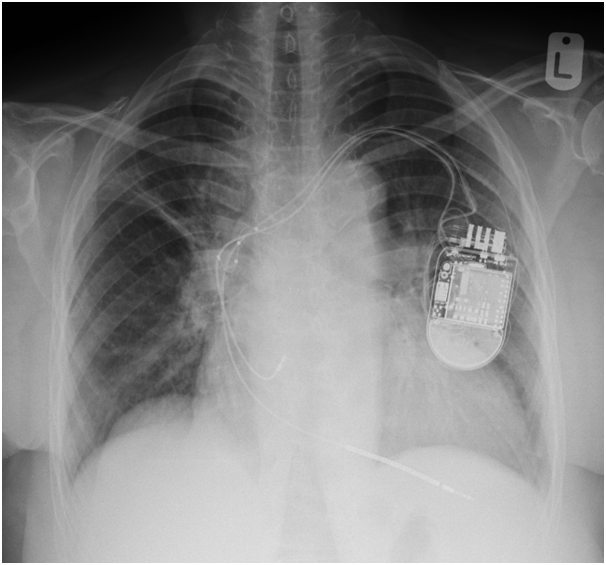

We were asked to see the patient, we reviewed her previous CXR post CRTD implantation and was (Figure 1) reviewed her procedure note which advocated the difficulty in securing LV lead deeply through lateral vein of the heart due to significant branch stenosis. The lead was then implanted in the posterolateral CS branch. Then, we requested a new CXR which showed the device slightly lower than implant position and displacement of LV lead higher in SVC (Figure 2).

Figure 1 CXR post CRTD implantation.